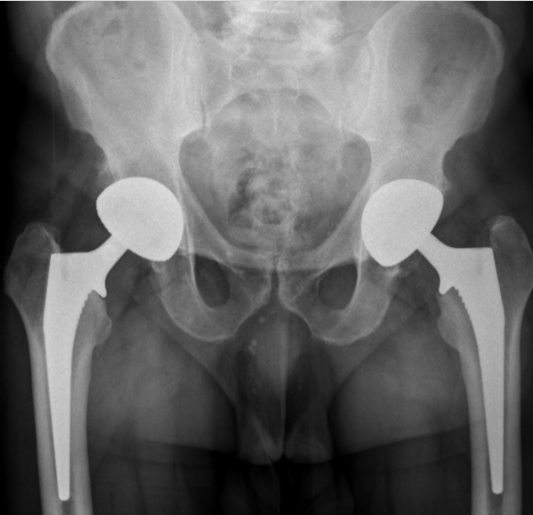

Recurrent Ceramic Femoral Head Fracture in Dual Mobility Total Hip Arthroplasty: A Case Report

Mohamad Khaled Ghannam , Elliot Sappey-Marinier , Michel Bonnin , Tarik Ait Si Selmi , Mohammad Alajji , Axel Schmidt

………………………………p.50-55